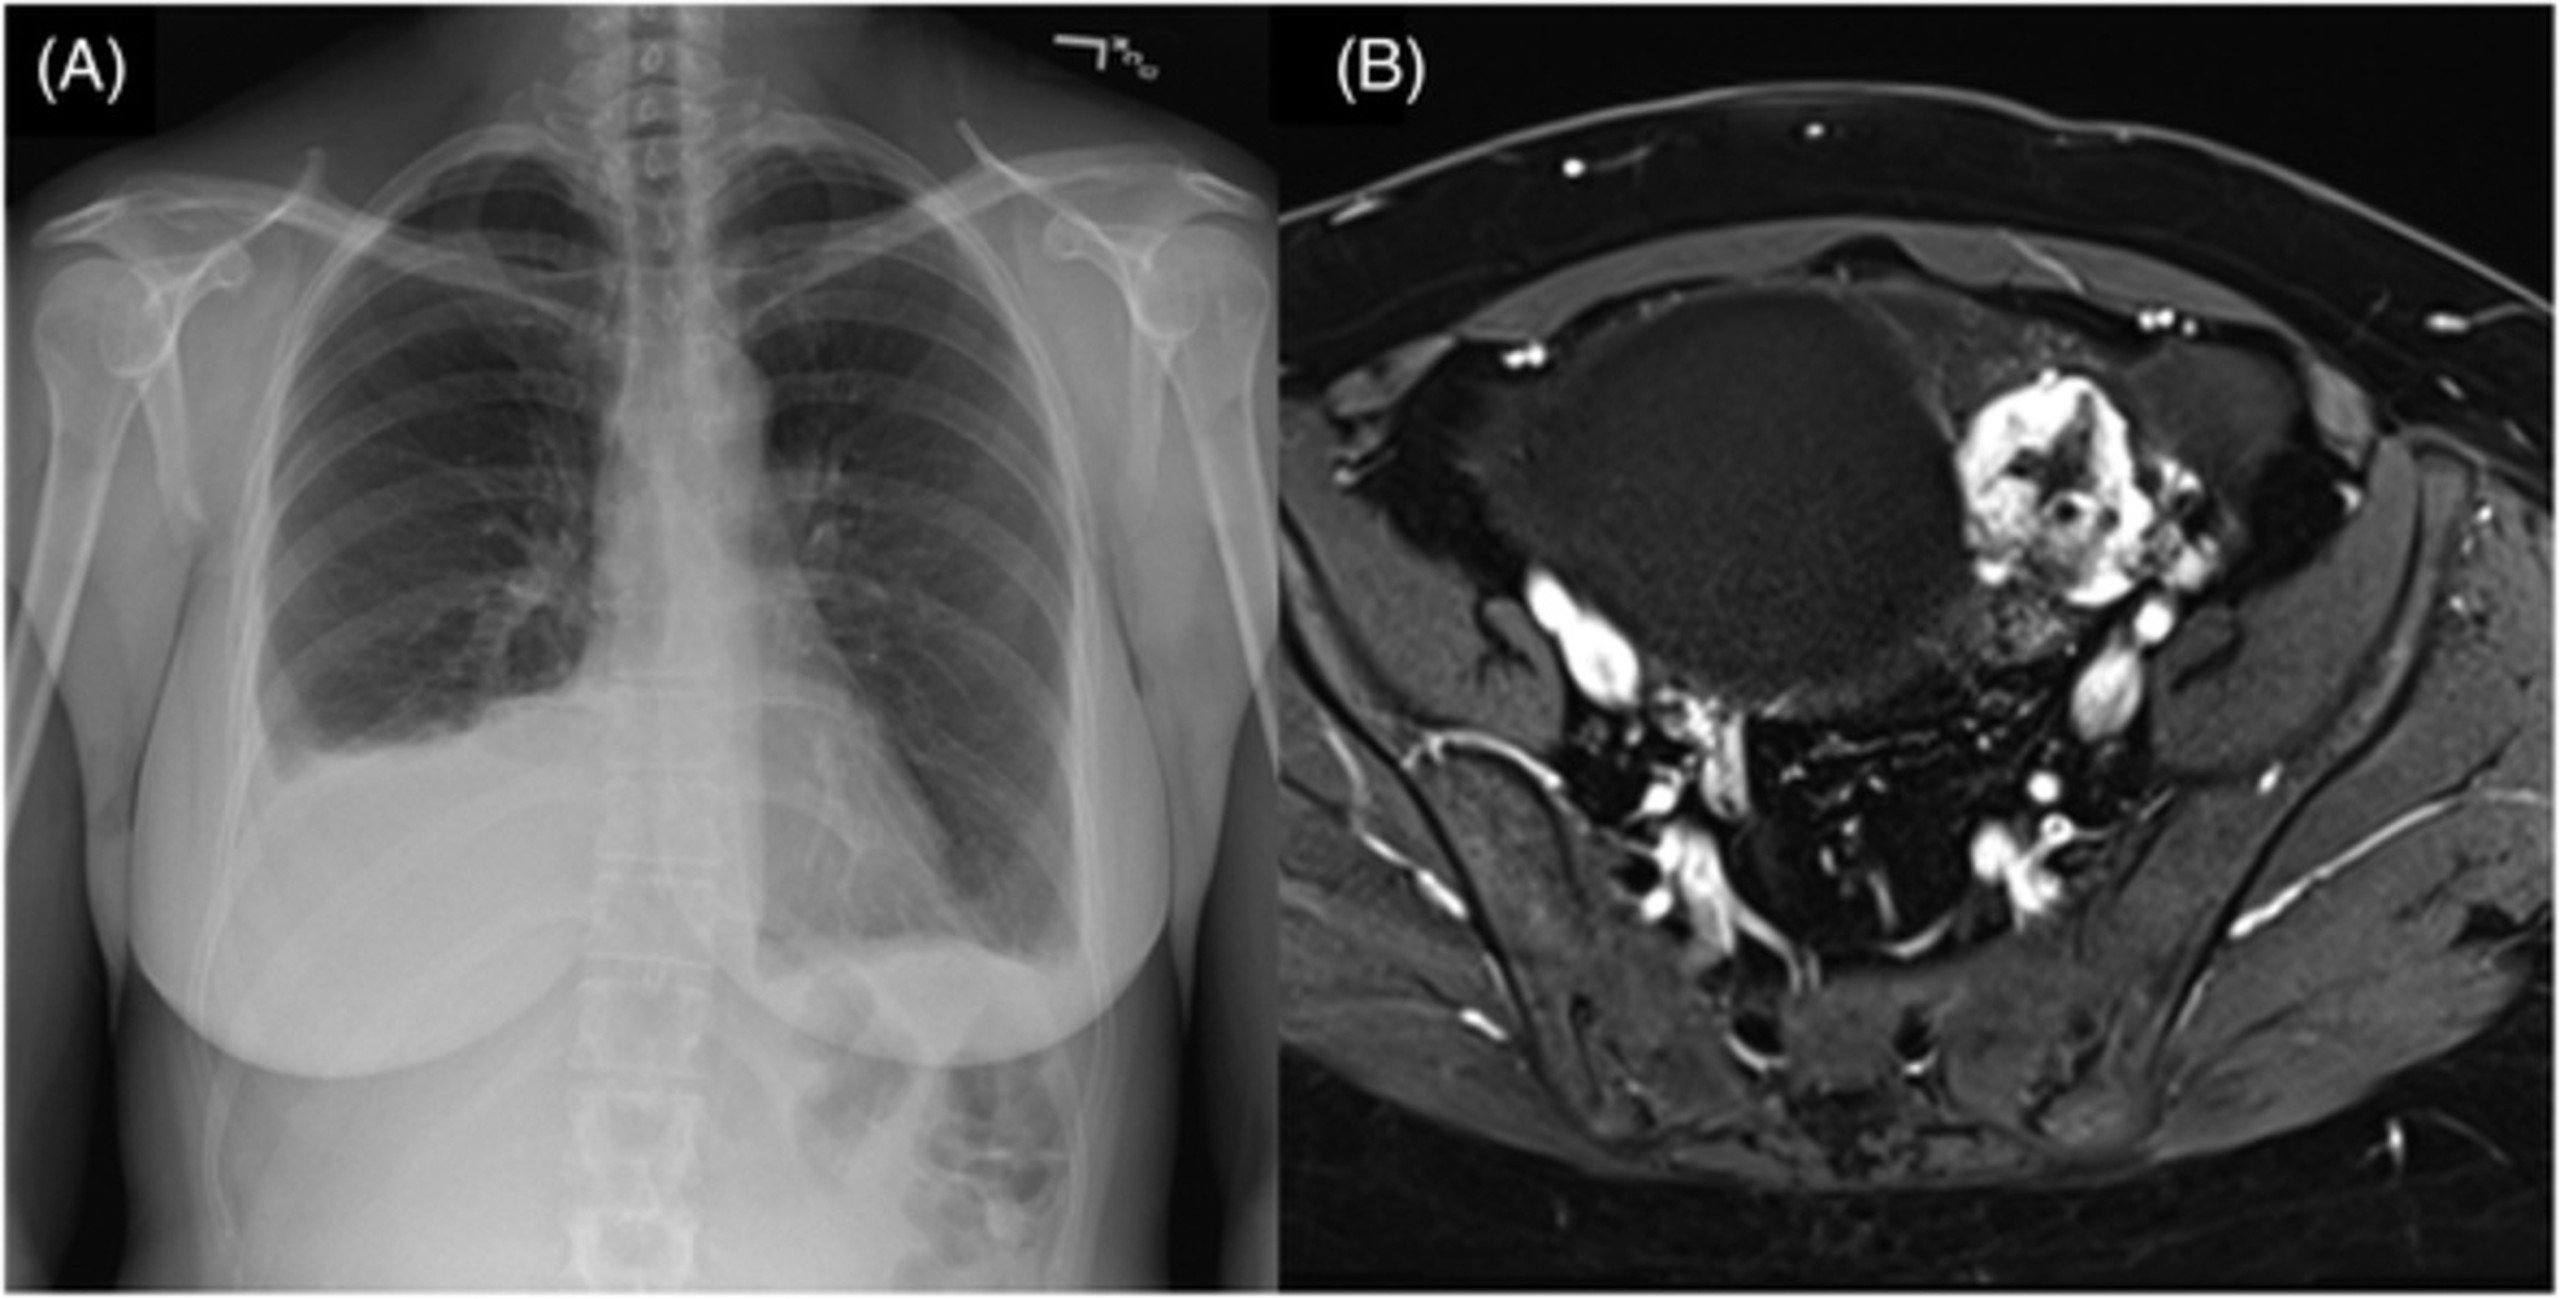

Các xét nghiệm chẩn đoán: